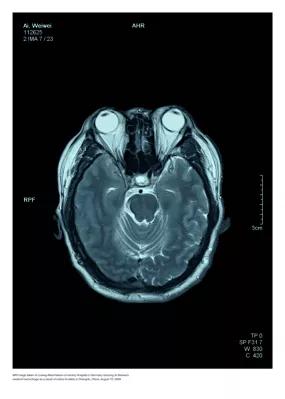

In Putins Hirn